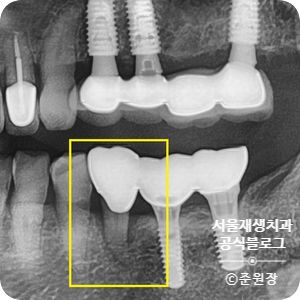

노란 네모 안에 있는 치아가 오늘의 주인공!

임플란트는 신경이 없는 티티늄 금속 덩어리이기 때문에 시린 느낌이 없습니다.

게다가, 골융합 과정을 통해 뼈에 단단히 고정되어 있기 때문에 여간해서는 흔들리는 일도 없지요.